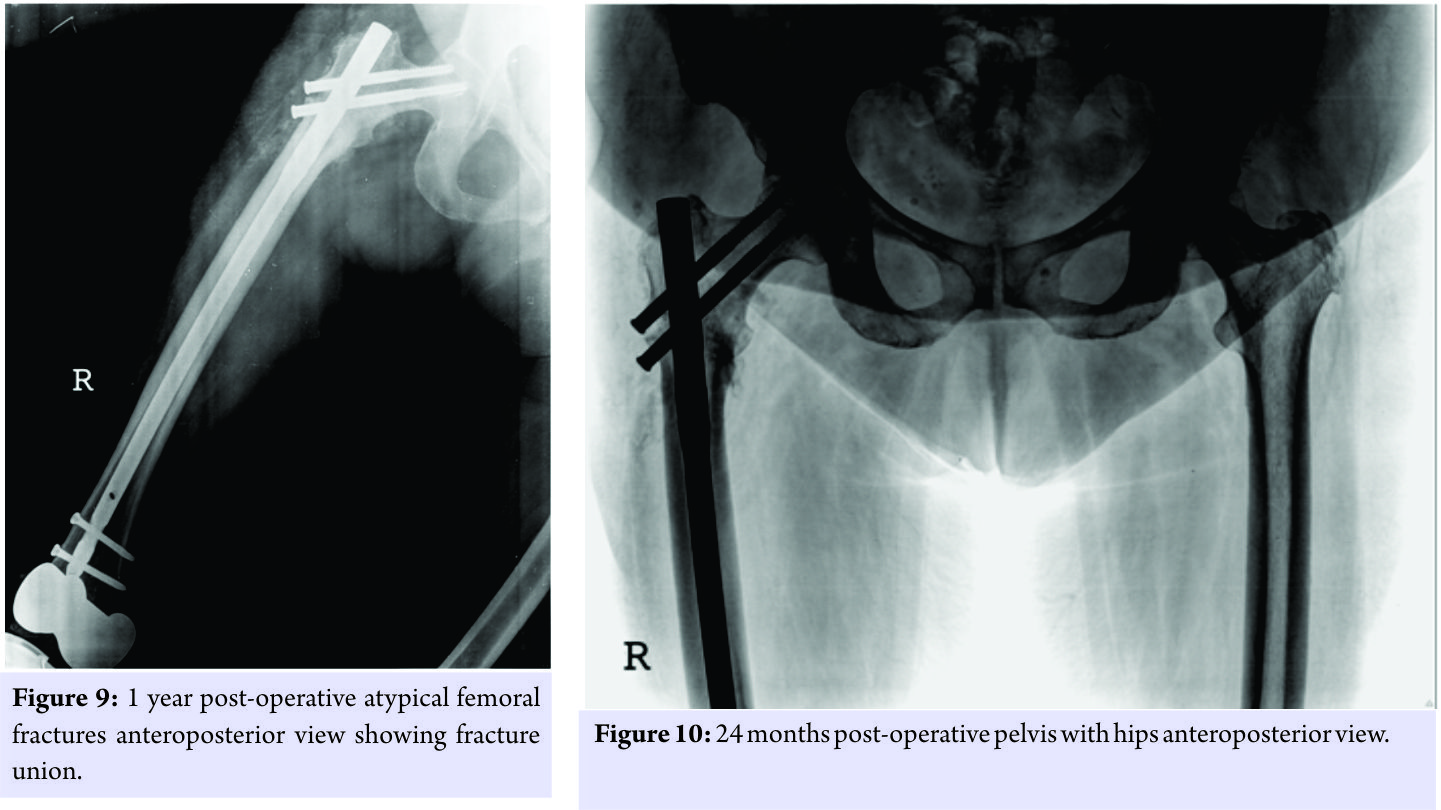

The knee replacement was unrelated to the sub-trochanteric fracture. For the subtrochanteric fracture of femur, regular follow-ups were done postoperatively with serial X-rays. Blood investigations were done, and serum calcium was 9.5mg/dl, and serum Vitamin D3 was 20ng/ml which was optimized with 6,00,000 IU of intramuscular Vitamin D3 and maintained by oral Vitamin D3 medications. At 3 months, the fracture was in delayed union (Fig. 5),and hence, the patient was started on injection Teriparatide 20mcg subcutaneous for a period of 18 months. The patient was kept non-weight bearing. The 6 months X-ray showed further progression in fracture healing (Fig. 6),and the patient was allowed partial weight bearing. In October 2013, 10 months after stopping Alendronate, she again came with the complaint of pain in the right side of the jaw; X-rays showed relapse of ONJ (Fig. 7) sequestrectomy was done on the right mandible. In February 2014, 13 months after stopping Alendronate, the patient came with the increased pain of the right mandible and was diagnosed as a fracture of the right mandible; the fracture was operated on and fixed with a plate in February 2014 (Fig.8). Meanwhile, the patient continued injection Teriparatide. At 1year postoperatively, the atypical femoral subtrochanteric fracture had healed (Fig. 9) and the patient was allowed full weight bearing. 24 months postoperatively, X-rays confirmed solid union of the atypical subtrochanteric femoral fracture (Fig.10). On recent review, the patient walks full weight bearing without the need of any support, with a normal gait and is completely asymptomatic as regards the femur as well as the jaw.

Meanwhile, the patient continued injection Teriparatide. At 1year postoperatively, the atypical femoral subtrochanteric fracture had healed (Fig. 9) and the patient was allowed full weight bearing. 24 months postoperatively, X-rays confirmed solid union of the atypical subtrochanteric femoral fracture (Fig.10). On recent review, the patient walks full weight bearing without the need of any support, with a normal gait and is completely asymptomatic as regards the femur as well as the jaw.